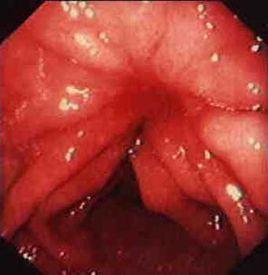

急性胃黏膜出血

病變主要侵及黏膜層,發生充血、多發性糜爛、點片狀或線狀出血及淺潰瘍,侵及部分或全胃黏膜,嚴重者可累及十二指腸甚至食管。潰瘍淺表、不侵犯黏膜肌層,僅有個別潰瘍可較深,甚至穿孔。組織學表現黏膜上皮層脫落、灶性壞死,充血水腫、出血,不象消化性潰瘍炎性細胞增多,及纖維組織增生。本病病變處血管常不形成血栓,故臨床上出血多見。

三、實驗室檢查。X線、鋇餐檢查常陰性。急性(24-48小時內進行)內鏡檢查,可見胃黏膜局限性或廣泛性點片狀出血,呈簇狀分布,多發性糜爛、淺潰瘍。好發於胃體底部,單純累及胃竇者少見,病變常在48小時以後很快消失,不留疤痕。